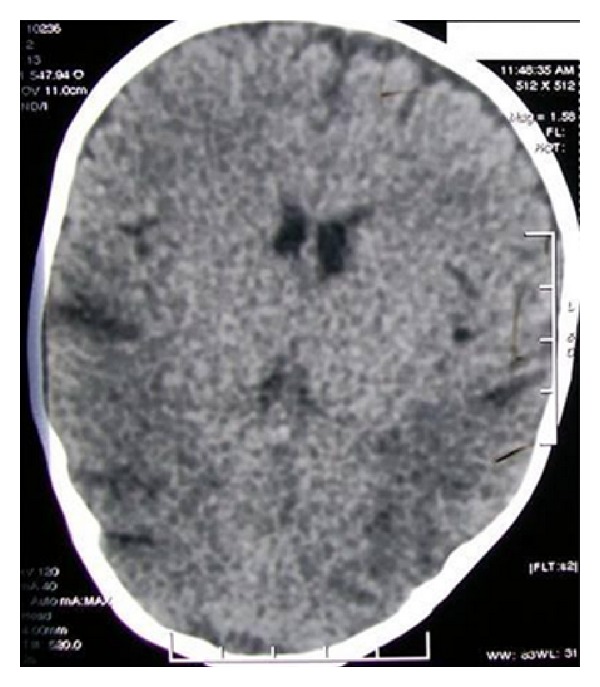

Electroencephalogram showed theta-delta range asymmetric background activity with intermittently sharp waves, sharp waves and slow waves seen over left hemisphere, and no further addition by photic stimulation. Metabolic workup done at the time was normal. Initial imaging workup with CT scan of brain revealed mild cerebellar atrophy with area of asymmetrical hypodensities in bilateral posterior parietal subcortical white matter (Figure 2). Subsequent magnetic resonance imaging showed asymmetric T2WI hyperintensities in bilateral temporoparietal cortex and subcortical white matter regions with involvement of the insular cortex with prominence of cerebellar folia suggesting cerebellar atrophy (Figure 3). At this point MRI diagnosis of urea cycle defects like citrullinemia and biotinidase deficiency were considered as differentials. Child was treated with biotin with no clinical improvement.

Figure 2.

Axial computerized tomography scan shows hypodensities in bilateral posterior parietal subcortical white matter.